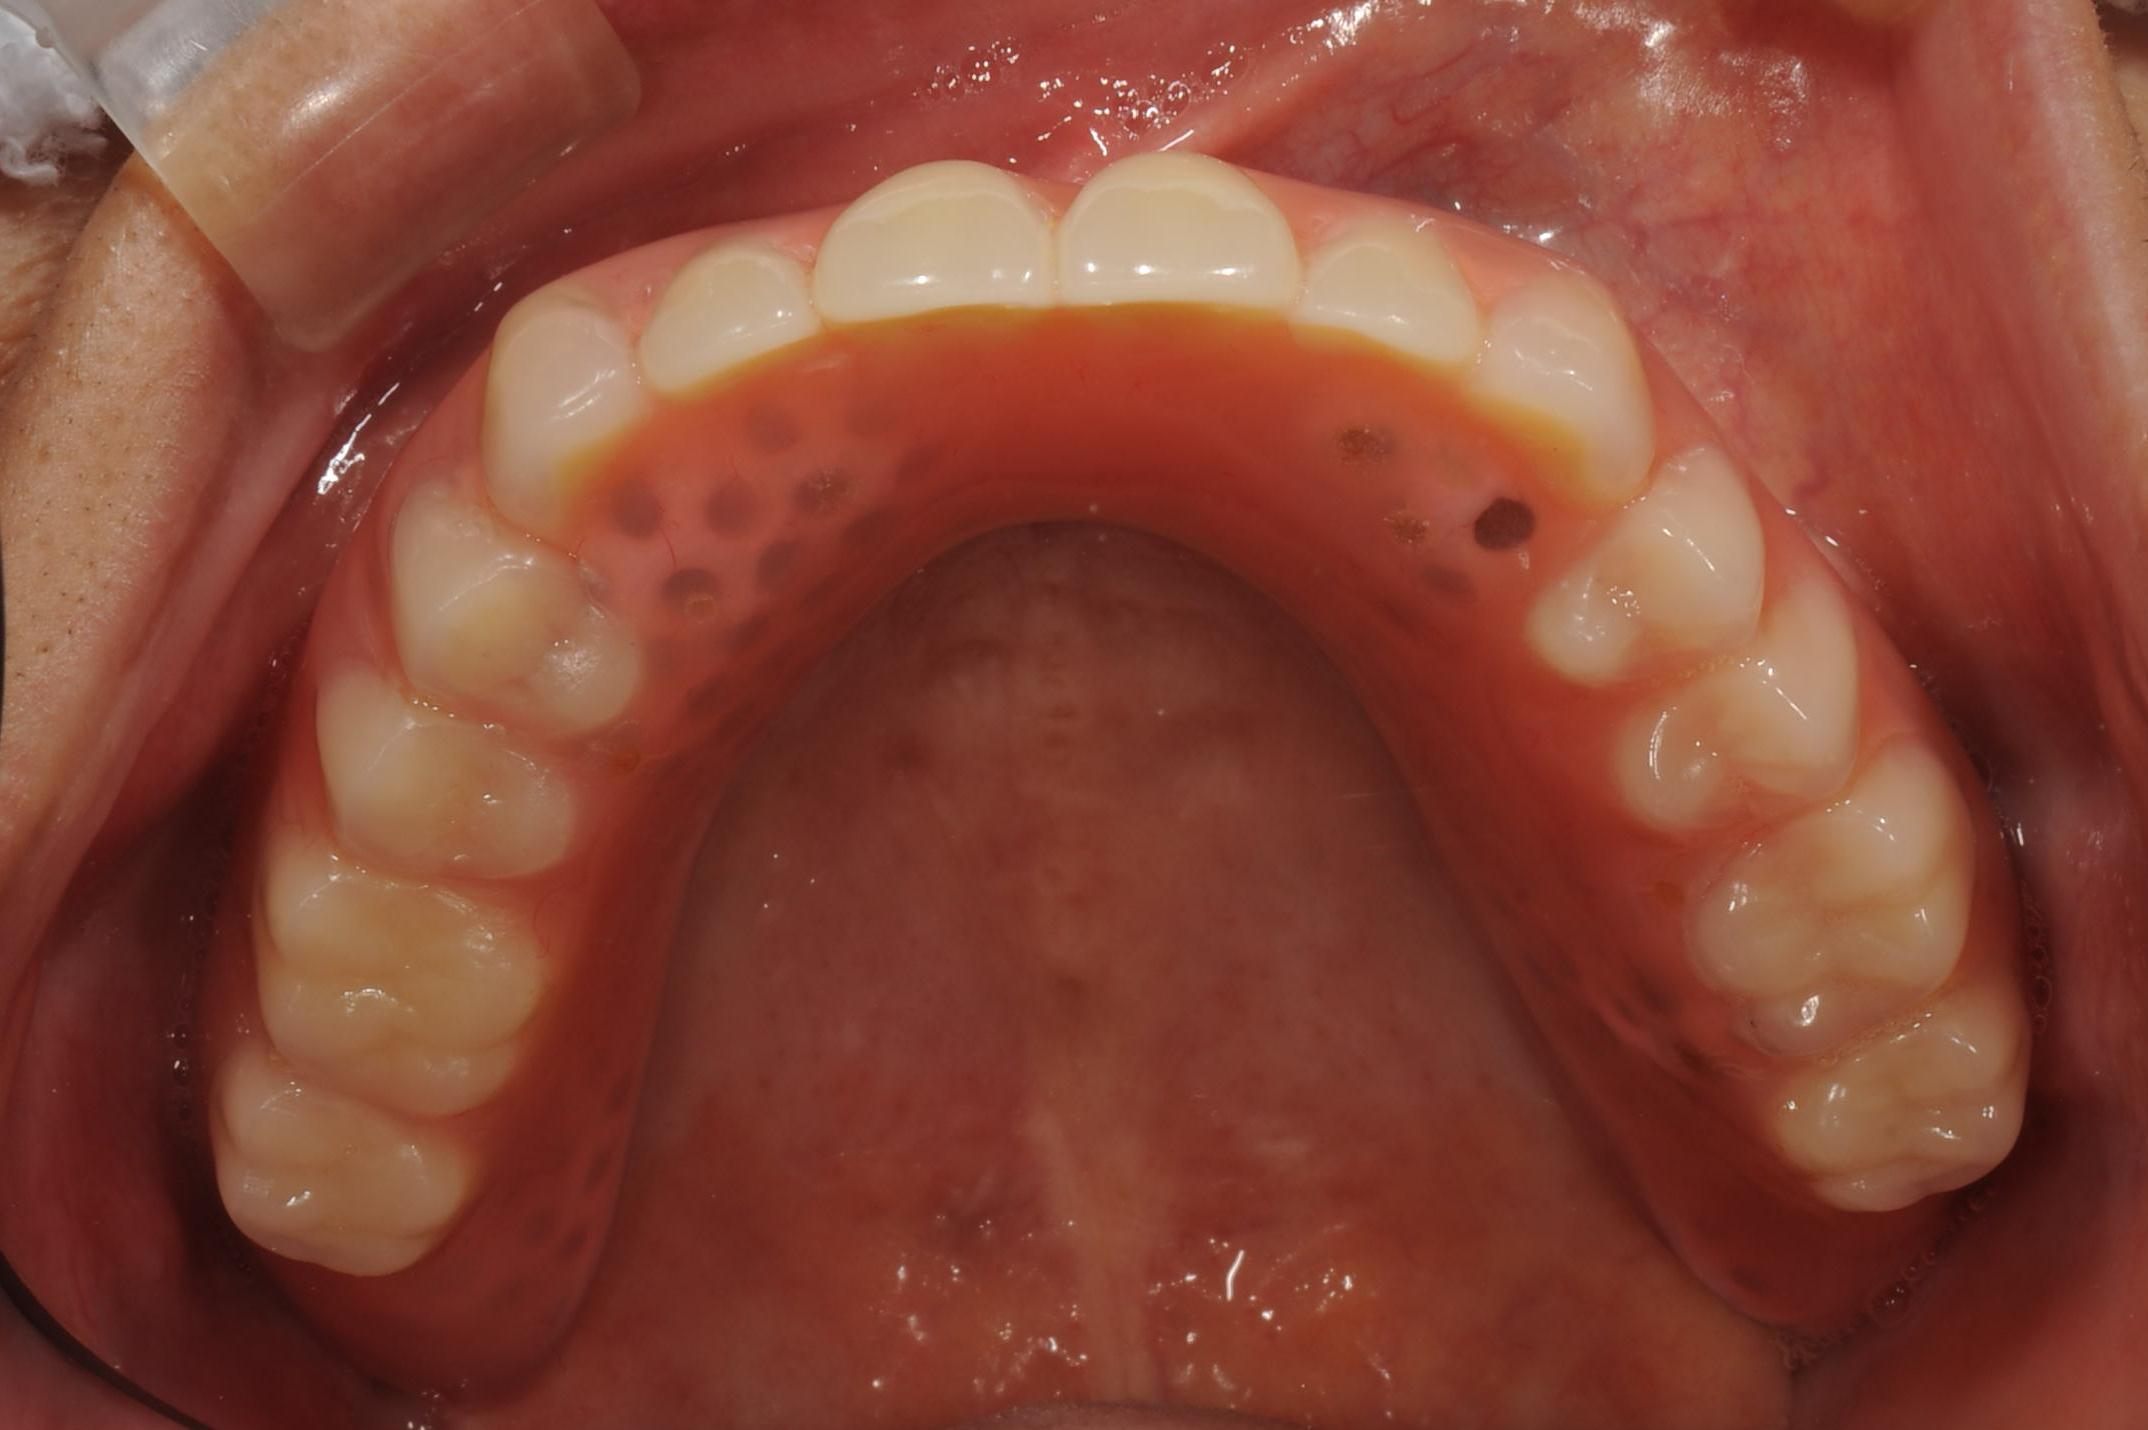

【入れ歯を外したお口の中】